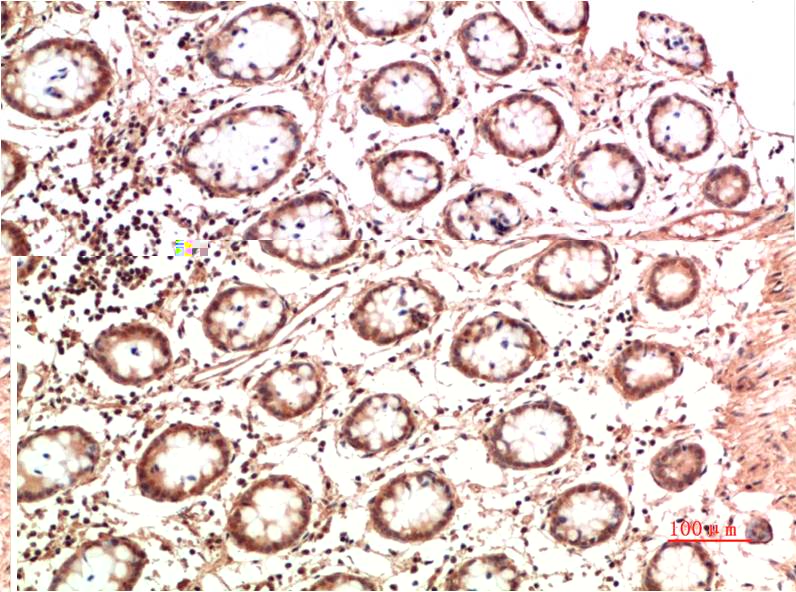

Applications :WB, IHC

| Recommended dilutions: | WB:1:1,000-2,000 IHC:1:200-500 |

| Specificity: | Antibody can detects endogenous STAT1 protein. |